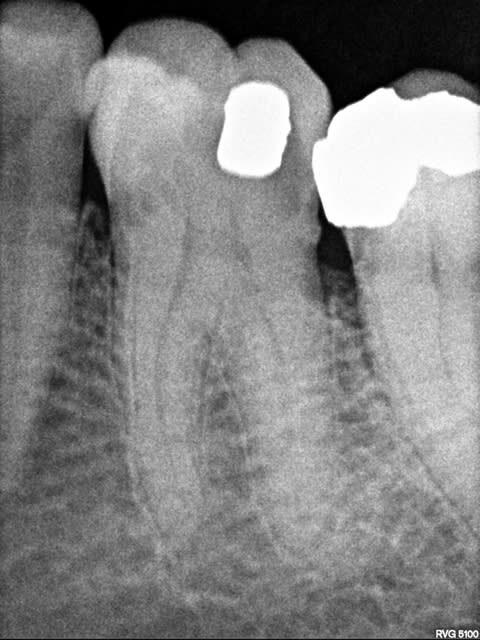

Patient de 65 ans qui consulte pour une fracture OL de 36.

La dent semble pouvoir recevoir un inlay mais je réalise une radio pour confirmer le traitement proposé.

On visualise bien la perte de substance mais aussi une lesion cervicale juxta-osseuse en mesial de 36.

cette resorption est ressentie a la sonde sous la gencive.

ça part en résorption externe pour moi, en mésial et distal.